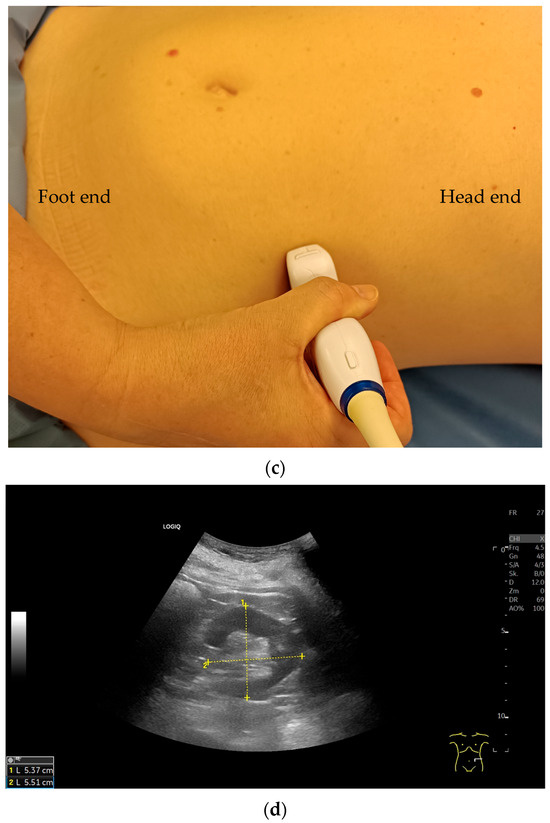

Variability of Renal Ultrasound Measurements: How Physician Experience and Patient Position Affect Measurement Accuracy?

J. Clin. Med. 2025, 14(16), 5840; https://doi.org/10.3390/jcm14165840 - 18 Aug 2025

This study was designed to investigate the variability of renal ultrasound measurements, focusing on the impact of physician experience and patient position. Background: Since decreased kidney length is considered an indicator for chronic renal disease, understanding measurement repeatability and reproducibility is crucial [...] Read more.

This study was designed to investigate the variability of renal ultrasound measurements, focusing on the impact of physician experience and patient position. Background: Since decreased kidney length is considered an indicator for chronic renal disease, understanding measurement repeatability and reproducibility is crucial for establishing effective diagnostic guidelines. Methods: Fifty healthy young adults underwent renal ultrasound scans performed by three examiners with varying levels of experience (12 years, 5 years, and 4 weeks). Renal length was measured at the level of the hilum in three patient positions: supine, lateral decubitus, and prone, using a 2–6 MHz convex probe (GE Logiq S8). Results: This study found that examiner experience significantly affected the results of sonographic measurements. However, the Interclass Correlation Coefficient analysis for all examiners demonstrated good reliability in most positions, with the highest values observed for the prone position. Measurements in the lateral decubitus position showed highest values, especially for the most experience examiner. The less experienced sonographers produced more variable results. Conclusions: Standardized patient positioning improves the accuracy and reproducibility of renal ultrasound measurements. The prone position offers a balance of reliability and practicality, especially for less experienced operators. Full article